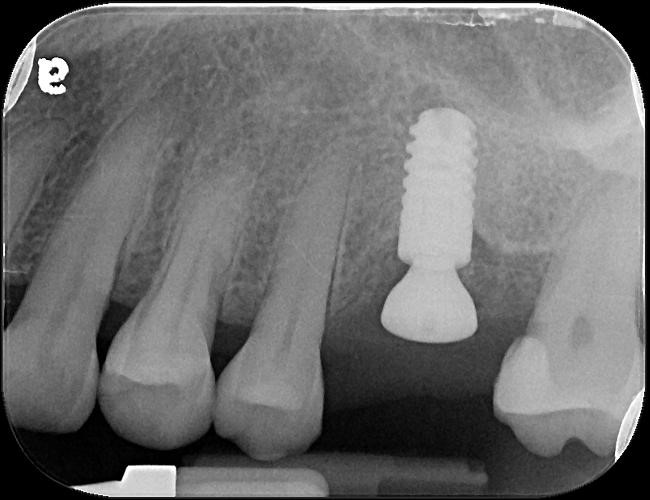

植牙後,角度良好

6個月後植牙骨整合